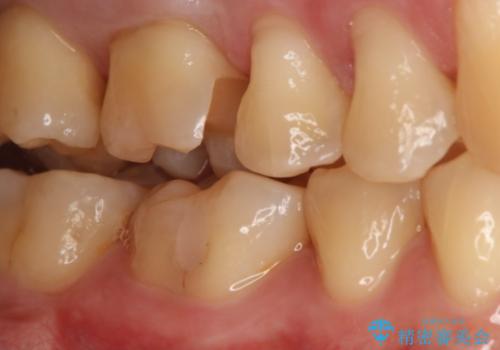

- 右上6番の銀歯をセラミックに変えたいと希望された患者様です。

切削量、形態を考慮し、セラミックインレーでの治療を計画しました。

銀歯と虫歯を除去した上でCRで裏層し形態を整えて印象を行っています。